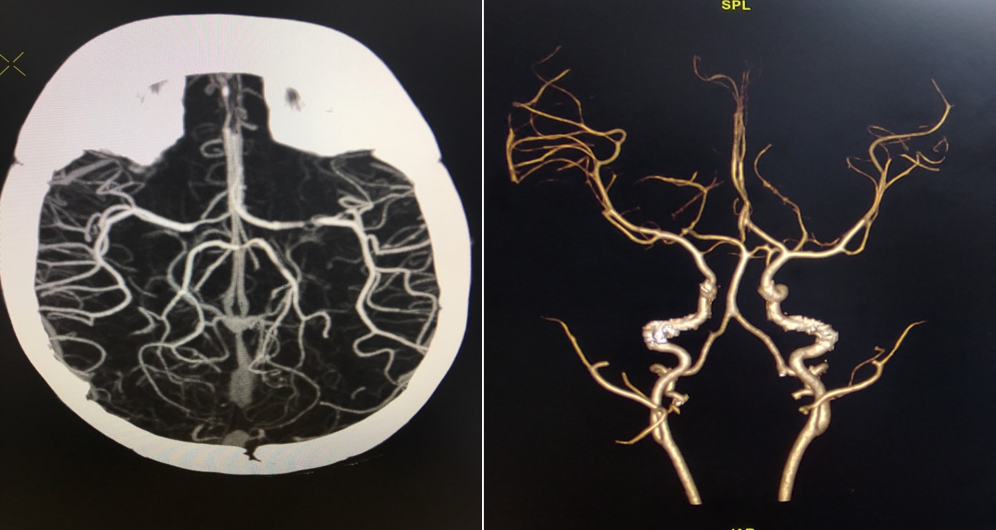

Ngày 12/3/2021, Bn N.M.Q sinh ngày 12/08/2020 ở An Dương - Hải Phòng nhập viện trong tình trạng quấy khóc, thóp phồng, nôn nhiều, không sốt, không co giật và được chỉ định chụp CLVT sọ não 64 dãy tại khoa Chẩn đoán hình ảnh Bệnh viện Trẻ Em Hải Phòng. Hình ảnh tụ máu dưới màng cứng bán cầu não bên phải nghi ngờ có dị dạng mạch não do bệnh nhân không có tiền sử chấn thương và không mắc các bệnh về máu. Sau đó được chỉ định chụp CLVT 64 dãy có dựng mạch não có tiêm thuốc cản quang Xenetix 300mgI/ml và cho kết quả: “Tụ máu dưới màng cứng bán cầu não bên phải nghi do rò động mạch - màng cứng (DAVF)”.

Hình ảnh chụp CLVT 64 dãy mạch não của Bn N M Q tại khoa Chẩn Đoán Hình ảnh: